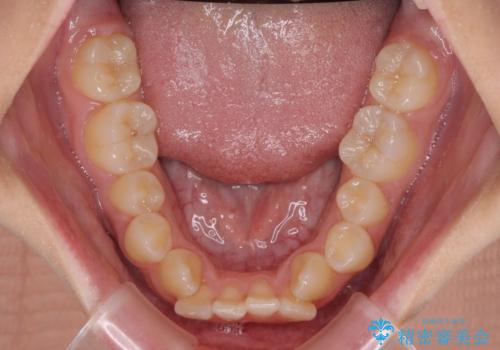

- 上下前歯のデコボコと八重歯を気にして来院された患者様です。

叢生を解消する際に出っ歯とならないようにするために、上下左右の小臼歯計4本を抜歯することとしました。